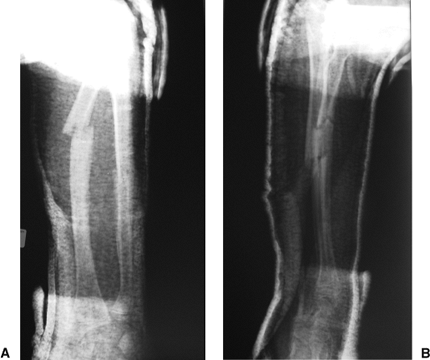

![]() |

|

Figure 11.21. AP (A) and lateral (B) radiograph of preoperative radius and ulna.

Figure 11.22. Preoperative AP (A) and lateral (B) radiograph after closed reduction.

Figure 11.23. Postoperative AP (A) and lateral (B) radiographs after closed nailing.